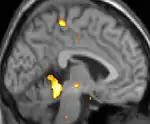

| Positron emission tomography (PET) shows brain areas being activated during pain. | ||

Positron emission tomography (PET) scans indicate the brain areas which are activated during attack only, compared to pain free periods. These pictures show brain areas that are active during pain in yellow/orange color (called "pain matrix"). The area in the center (in all three views) is specifically activated during CH only. The bottom row voxel-based morphometry (VBM) shows structural brain differences between individuals with and without CH; only a portion of the hypothalamus is different.[36]